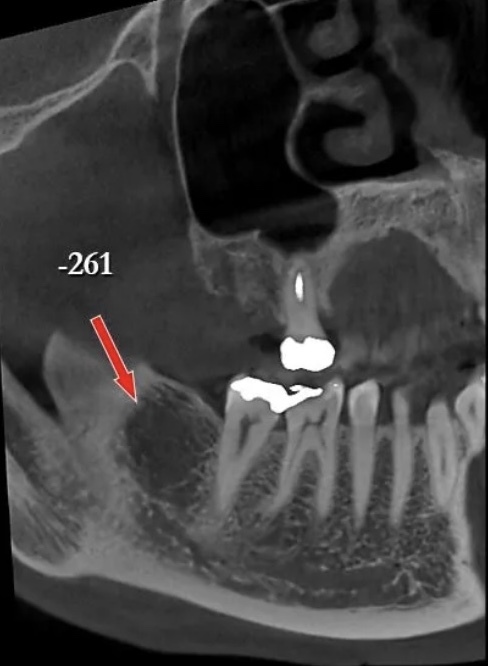

Cavitations

A cavitation is a “hole” in the jawbone where a tooth was extracted, but healthy bone never filled in. This dark, hollow area of bone is the perfect breeding ground for parasites, fungi, bacteria, and viruses. Unfortunately, when most teeth are extracted, the periodontal ligament that attaches the tooth to the jawbone remains. Because this ligament is left behind, the body never senses that the tooth is gone, and therefore new bone does not grow back.